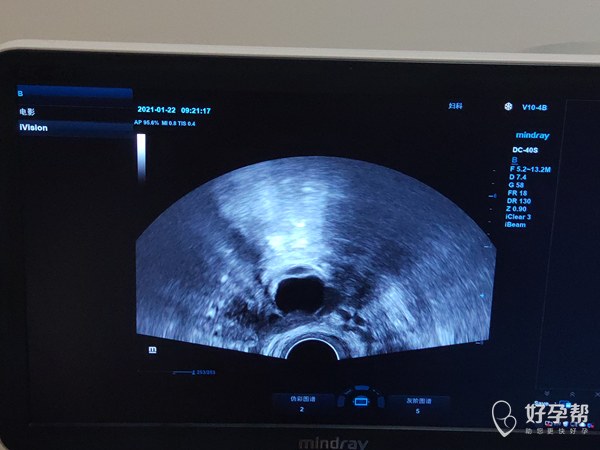

1月22早上9点去监测卵泡做得阴超医生操作过

1月22早上9点去监测卵泡,做得阴超,医生操作过程中感觉有点疼痛。

1月23日下午4点左右阴道出血,小护垫都浸湿了。之前做阴超没有这种情况,这次会是什么原因。(有性生活才一年)